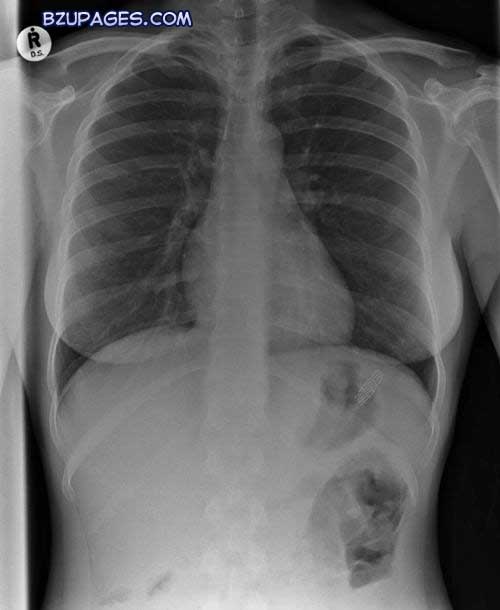

An X-ray of a bullet (conical object at centre left) embedded in the chest of a patient